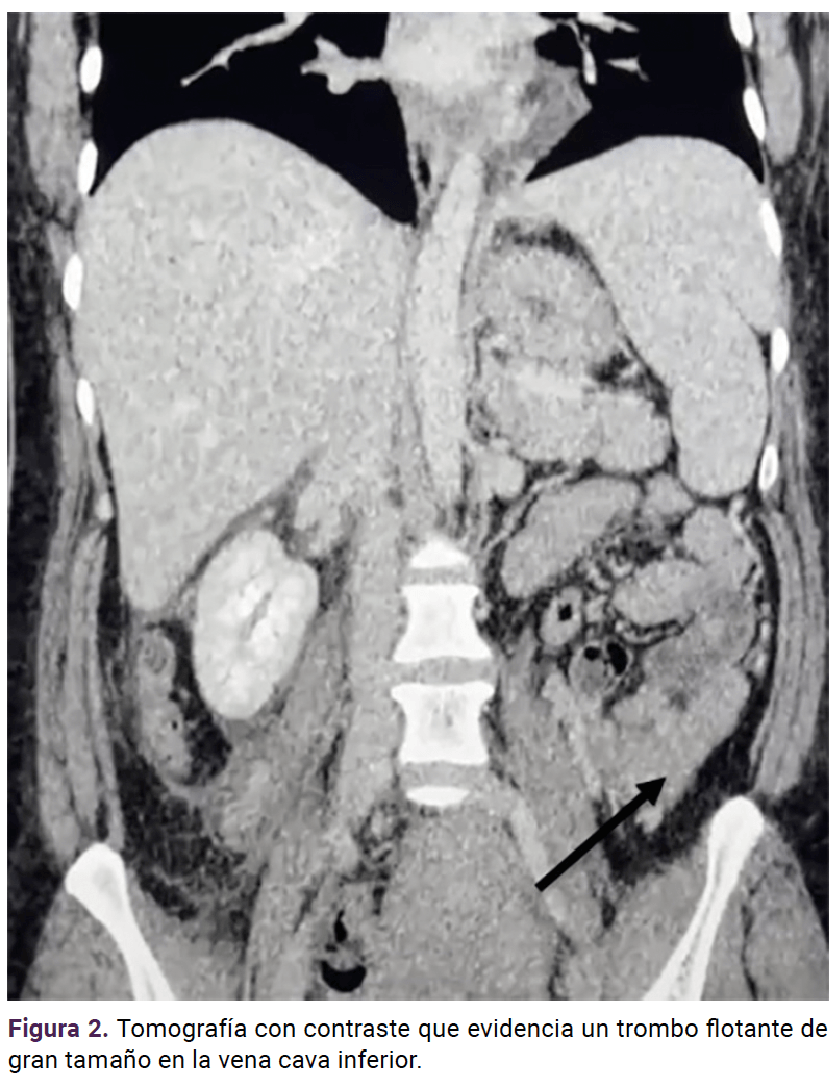

En la fase venosa de la tomografía contrastada se identificó una imagen hipodensa sugerente de trombo de la vena cava inferior, dependiente de la íntima vascular que obstruía el 11% de la vena cava inferior y el 100% de la vena ovárica derecha, así como el reconocimiento del ovario derecho con aumento de tamaño y de la densidad en la masa periovárica; además de borramiento de la grasa adyacente con un paso hipocaptante al medio de contraste; con ello se integró el diagnóstico de trombosis de la vena ovárica.

<strong>Figura 2</strong>

Figura 2

Hoy día, la tomografía computada con contraste (venografía) es el estudio de elección por excelencia. Este método de imagen también permite observar la extensión total del trombo y la vena renal, aunque en algunas circunstancias puede ser difícil de visualizar, debido a la mezcla de sangre con contraste y la no contrastada en las venas renales. La típica imagen diagnóstica en la tomografía contrastada consiste en un defecto de llenado, aumento de tamaño del vaso y reforzamiento de la pared, conocidos como los criterios de Zerhouni. La sensibilidad de la tomografía contrastada es del 77 al 100% y la especificidad del 62 al 99%.8,14